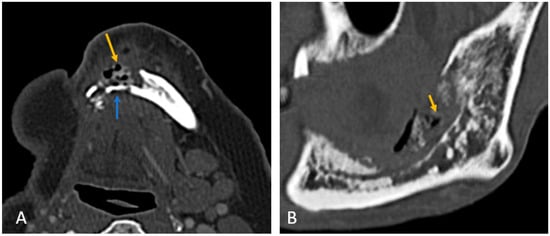

• Bone involvement: 18 patients had only mandibular ORN, while 16 had combined mandibular and maxillary involvement (Figure 1B). Isolated maxillary ORN was observed only once (Figure 1A). Bilateral maxillary involvement alone was not observed.

Figure 1. (A) Coronal CT image showing involvement of bilateral upper alveolus (white arrow) and mandible with areas of cortical erosion, trabecular thickening, and sclerosis (black arrow). (B) Coronal CT image showing extensive ORN of the left maxilla—seen as destruction and collapse (arrow).